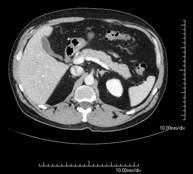

- TC Abdominopélvico Prueba diagnóstica que consiste en obtener imágenes bi y tridimensionales del abdomen y de la pelvis de alta definición anatómica (estructuras óseas, estructuras vasculares, hígado, páncreas, vesícula biliar, riñones, glándulas suprarrenales, bazo, intestino delgado y grueso, vejiga, útero y ovarios, próstata y vesículas seminales, uréteres, etc.) mediante el empleo de un equipo de TC (Tomografía Computarizada). La mayoría de estudios requieren el empleo de contraste yodado. Prueba diagnóstica que consiste en obtener imágenes bi y tridimensionales del abdomen y de la pelvis de alta definición anatómica (estructuras óseas, estructuras vasculares, hígado, páncreas, vesícula biliar, riñones, glándulas suprarrenales, bazo, intestino delgado y grueso, vejiga, útero y ovarios, próstata y vesículas seminales, uréteres, etc.) mediante el empleo de un equipo de TC (Tomografía Computarizada). La mayoría de estudios requieren el empleo de contraste yodado.

- TC Páncreas Prueba diagnóstica que consiste en obtener imágenes bi y tridimensionales del páncreas de alta definición anatómica mediante el empleo de un equipo de TC (Tomografía Computarizada). Se realiza el estudio antes y después del empleo de contraste yodado en diferentes "fases pancreáticas" para poder valorar todas las estructuras (parénquima pancreático, conducto pancreático o de Wirsung, unión bilio-pancreática, colédoco, arterias pancreáticas, arteria y vena esplénicas, duodeno, etc.). Está especialmente indicado ante la sospecha de lesión pancreática, en pacientes con pancreatitis aguda o crónica, etc. Prueba diagnóstica que consiste en obtener imágenes bi y tridimensionales del páncreas de alta definición anatómica mediante el empleo de un equipo de TC (Tomografía Computarizada). Se realiza el estudio antes y después del empleo de contraste yodado en diferentes "fases pancreáticas" para poder valorar todas las estructuras (parénquima pancreático, conducto pancreático o de Wirsung, unión bilio-pancreática, colédoco, arterias pancreáticas, arteria y vena esplénicas, duodeno, etc.). Está especialmente indicado ante la sospecha de lesión pancreática, en pacientes con pancreatitis aguda o crónica, etc.

- PAAF (Punción) Abdominal guiada por TC Consiste en obtener una muestra de tejido de una determinada lesión localizada en la cavidad abdominal. Para ello se administra anestesia local sobre la zona de la punción, la cual se realiza con agujas de fino calibre. Todo el procedimiento se realiza controlado con imágenes obtenidas por Tomografía Computarizada (TC) en varios momentos de la punción, mediante el uso de un equipo de Fluroscopia-TC. Tras la prueba, el paciente permanece unas horas hospitalizado para controlar su evolución. Es necesario aportar pruebas de coagulación antes de la punción. Consiste en obtener una muestra de tejido de una determinada lesión localizada en la cavidad abdominal. Para ello se administra anestesia local sobre la zona de la punción, la cual se realiza con agujas de fino calibre. Todo el procedimiento se realiza controlado con imágenes obtenidas por Tomografía Computarizada (TC) en varios momentos de la punción, mediante el uso de un equipo de Fluroscopia-TC. Tras la prueba, el paciente permanece unas horas hospitalizado para controlar su evolución. Es necesario aportar pruebas de coagulación antes de la punción.

- Biopsia abdominal guiada por TC Consiste en obtener una muestra de tejido de una determinada lesión localizada en la cavidad abdominal. En ocasiones se realiza bajo sedación, con la ayuda del equipo de anestesia. Se utilizan agujas que permiten la obtención de un cilindro de la lesión a estudiar, que se enviará a Anatomía Patológica para su análisis histológico. Todo el procedimiento se realiza controlado con imágenes obtenidas por Tomografía Computarizada (TC) en varios momentos de la biopsia, mediante el empleo de Fluoroscopia-TC. Tras la prueba, el paciente permanece hospitalizado para controlar su evolución. Es necesario aportar pruebas de coagulación antes de la punción. Consiste en obtener una muestra de tejido de una determinada lesión localizada en la cavidad abdominal. En ocasiones se realiza bajo sedación, con la ayuda del equipo de anestesia. Se utilizan agujas que permiten la obtención de un cilindro de la lesión a estudiar, que se enviará a Anatomía Patológica para su análisis histológico. Todo el procedimiento se realiza controlado con imágenes obtenidas por Tomografía Computarizada (TC) en varios momentos de la biopsia, mediante el empleo de Fluoroscopia-TC. Tras la prueba, el paciente permanece hospitalizado para controlar su evolución. Es necesario aportar pruebas de coagulación antes de la punción.